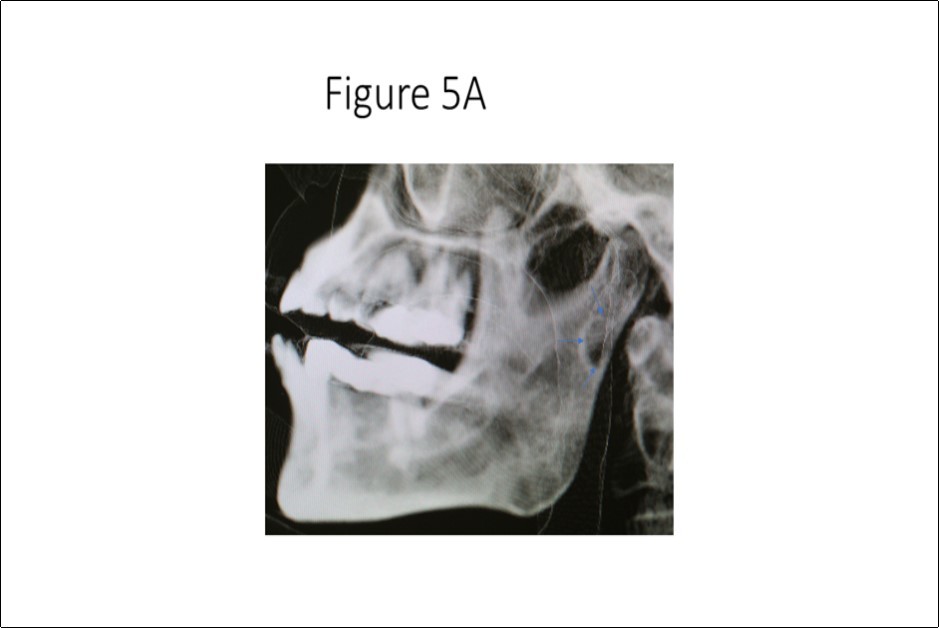

Maxillofacial examination was unremarkable. No facial swelling, masses or asymmetry was observed. The TMJ examination was normal. No pain or tenderness to digital palpation was observed in the right preauricular region. Oral examination of the patient was unremarkable. No trismus was observed as the maximal interincisive opening was greater than 40.0mm. No anterior or posterior open bite was observed. Imagining studies to rule-out intraosseous neoplastic lesions and arrive at a definitive diagnosis consisted of a panoramic radiograph and cone beam CT scan (120 kVp, 5 mA, 7.4 sec). Panoramic radiograph revealed a unilocular, well-circumscribed radiolucency in the right subcondyalar region of the mandible that was close to the posterior border of the condylar neck (Figure 2). Cone beam CT scan (i-CAT FLX, Imaging Sciences, Hatfield, PA) imaging revealed a well-defined unilocular, elliptical shaped radiolucent lesion on the medial surface of the right subcondylar neck of the mandible (Figure 3, Figure 4, Figure 5). The elliptical shaped unilocular lesion involved almost the entire horizontal dimension of the subcondylar neck (Figure 4). Figure 5 shows the three-dimensional CT scan reconstruction (i-CAT FLX, Imaging Sciences, Hatfield, PA) of the medial defect in the subcondylar region of the mandible. Based on knowledge of clinical head and neck anatomy and imaging studies, no treatment was indicated as the diagnosis was consistent with a variant of a Stafne bone cavity of the right subcondylar neck near the parotid gland and not a pathological condition. The patient was informed about the risk of condylar neck fracture due to the critical size of the SBC.

Figure 5A.Three-dimensional cone beam CT scan reconstruction revealing osseous defect in medial cortex of right subcondylar neck of mandible.